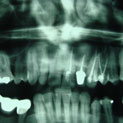

Aunque su estirpe anatomopatológica sea benigna, son quistes que en algunos pacientes provocan grandes destrucciones maxilares, porque crecen de forma asintomática durante años.

Su cirugía es sencilla y está basada en la extracción del quiste con criterios conservadores, y en la reconstrucción del defecto creado por la limpieza quirúrgica.

Para la reconstrucción, aconsejamos hacerlo en la misma intervención y con las bases de ingeniería tisular de la regeneración ósea guiada. Utilizamos como material óseo inductor el fosfato tricálcico tipo beta, mezclado con sangre del paciente y protegido con membrana de regeneración reabsorbible.